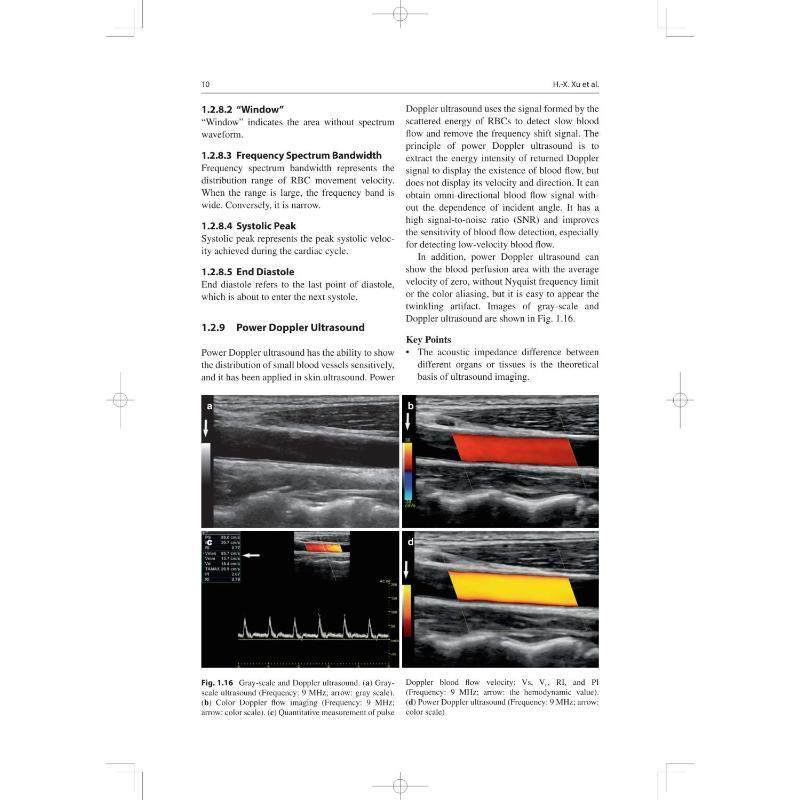

dermatology上海科学技术出版 RT69 ultrasoundin Diagnostic 社医药卫生图书书籍 包邮